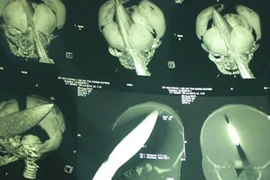

Ca phẫu thuật và hậu phẫu được xem là thần kỳ bởi lưỡi dao dài 26 cm đã đâm thấu não bé trai 11 ngày tuổi bị đâm xuyên đầu.

Khoa Cấp cứu, BV nhi đồng 1 tiếp nhận bệnh nhi sơ sinh 11 ngày tuổi, vì bị dao đâm xuyên sọ.